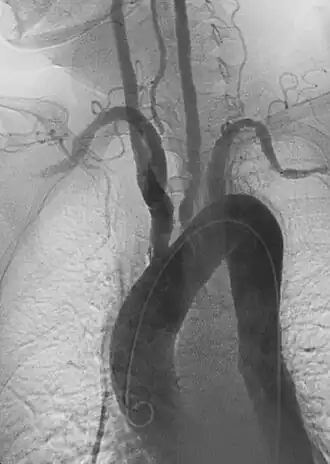

L'imagerie artérielle est un temps fort du diagnostic de maladie de Takayasu. L'echodoppler, l'artériographie, l'angioscanner, l'angioIRM se complètent[11].

Les images retrouvées sont multiples, étagées, avec des aspects de coarctation, des images « en queue de radis », sténoses, occlusions, anévrismes divers.